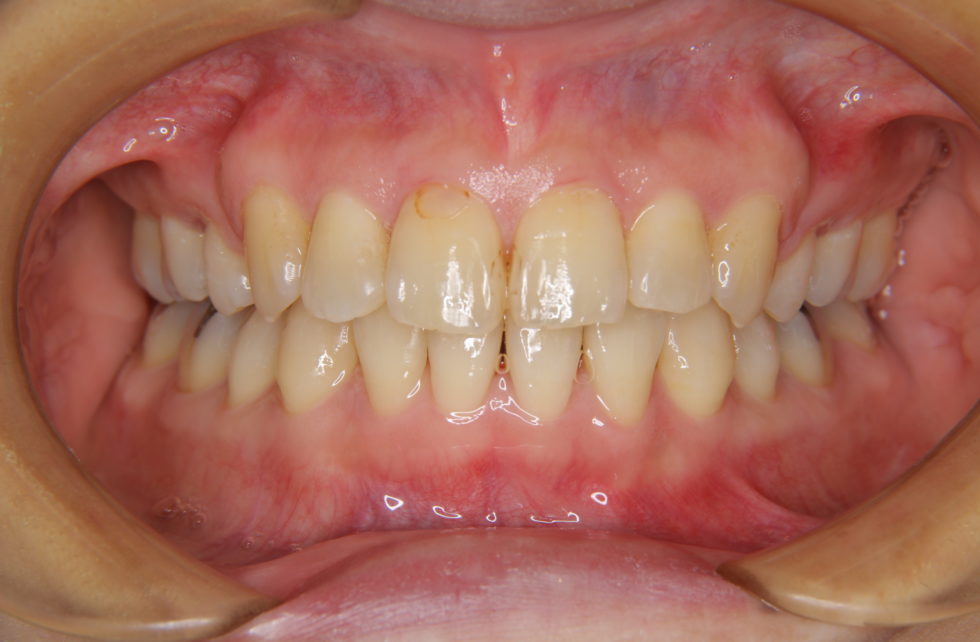

初診時年齢36歳女性。上下顎前歯の叢生を主訴として来院された。

上下の犬歯が唇側転位となっていた。上顎小臼歯、下顎歯患者さんの希望もあり犬歯を抜歯していただき上顎舌側、下顎唇側マルチブラケット装置を使用して動的治療を行った。   動的治療期間は1年4か月間